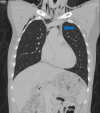

Tracheobronchial injury (TBI) is a rare life-threatening injury that can result from either penetrating or blunt trauma. Treatment may be surgical or conservative, but the evidence regarding which is the best approach is still very scarce. This case report describes the successful conservative management of a 32-year-old male with a traumatic tracheal laceration. The alarming signs and symptoms, the imaging modalities of choice, the rationale behind the treatment strategy, and the most common complications are detailed here. Through this case, the authors wish to highlight the features that should lead to the suspicion of this potentially fatal traumatic injury, as well as raise awareness on how to adequately manage these patients.